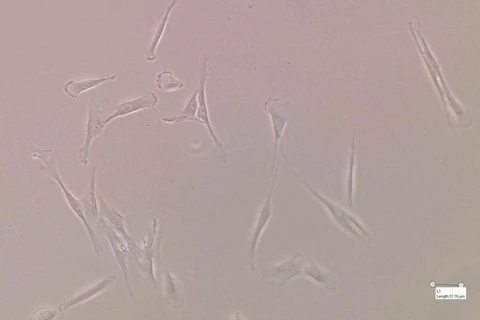

Atualmente, Moira tem um grande desafio em mãos. Ela faz parte da equipe que pesquisa o uso células-tronco para auxiliar no tratamento de casos graves da Covid-19. Moira trabalha com células-tronco mesenquimais, coletadas de dentes saudáveis de doadores jovens. Uma vez isoladas, as células são multiplicadas no Centro de Processamento Celular (CPC), da Curityba Biotech, e são infundidas em pacientes acometidos de síndrome respiratória aguda grave e que estejam internados em Unidade de Terapia Intensiva (UTI).

"As células-tronco mesenquimais são células imaturas que, por ainda não estarem especializadas, são capazes de se multiplicar inúmeras vezes e também secretam muitas substâncias ativas. Algumas das substâncias que as células-tronco mesenquimais produzem têm capacidade imunomoduladora, ou seja, são capazes de reequilibrar essa resposta exagerada do organismo, orquestrando os processos de reparo", detalha.